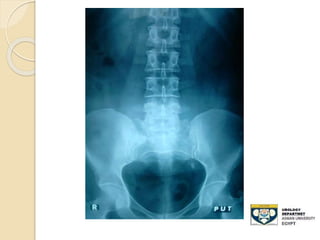

KUB film

 - Advantages:

◦ 80-90% of stones are radio-opaque

◦ Minimal radiation

 Disadvantages:

◦ Radiolucent stone

◦ Easy to miss mid-ureteral stones over the

sacrum

◦ Bowel gas can obscure its efficacy

◦ Cannot differentiate , Stones,Calcified LN

,

◦ Sensitivity: 50-70%

STONE UPPER THIRD URETER